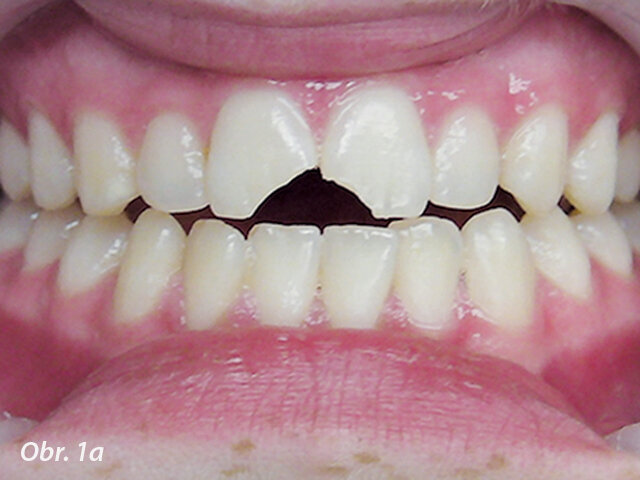

Obr. 1a: Klinický případ dvou nekomplikovaných fraktur korunky, kdy dva ulomené fragmenty byly nalezeny a znovu připevněny (fotografie poskytnuty American Association of Endodontists)

Fraktury korunky

První, co je třeba udělat u jakékoliv korunkové nebo korunko-kořenové fraktury, je pokusit se najít odlomený fragment zubu. S moderní bondovací technologií je možné znovu spojit odlomený fragment se zbytkem zubu, což je esteticky nejlepší řešení. Ještě před připojením fragmentu zubu musí být tloušťka vrstvy zubu mezi pulpou a povrchem zhodnocena radiologicky a klinicky. Pokud zbývá alespoň 0,5 mm dentinu, není nutno místo překrývat ochrannou podložkou. Pokud je stanoveno, že zbytkový dentin je méně než 0,5 mm široký, je doporučeno překrýt oblast fraktury nejblíže u pulpy podložkou a tvarově přizpůsobit spojovací plochu fragmentu. Pokud byl fragment zubu držen v suchu, měl by být rehydratován v destilované vodě nebo slině po dobu 30 minut před spojováním, což zvýší vazebnou sílu (obr. 1a–c).